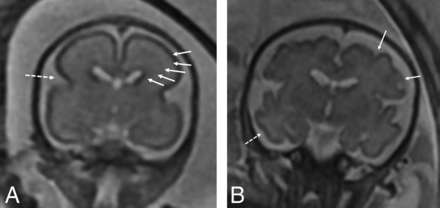

Findings recorded on the fetal MR imaging were germinal matrix hemorrhage, the presence of restricted diffusion when performed, ventriculomegaly, and enlarged extra-axial spaces. Enlargement of the extra-axial spaces was determined when the distance between the inner margin of the calvaria and the frontal or parieto-occipital region was greater than the values for gestational age.8,9 Ventriculomegaly was diagnosed when the maximum width of the lateral ventricles at the level of the atrium measured >10 mm.10 The presence of maturational delay, engorged dural venous sinuses, and parenchymal signal abnormality was recorded by a senior neuroradiologist (B.M.K.-F.). Brain maturation was assessed comprehensively on T2-weighted images by comparison with a published and widely used timeline of brain development, germinal matrix involution, myelination, and cortical infolding/sulcation.11 Brain maturation was dichotomously graded as normal or delayed. Figure 1 highlights a few of the maturational changes that were assessed.

A, Coronal T2-weighted image of a fetus with CDH at 24 weeks demonstrating expected maturation with the presence of the interhemispheric and Sylvian fissure (dashed arrow), but with an otherwise smooth appearance of the frontal lobes. There is expected visualization of the migrating neurons as evidenced by alternating dark and bright bands in the cerebral parenchyma (arrows) corresponding, from inside out, to the ventricular zone/germinal matrix, periventricular fiber rich zone, intermediate zone, subplate zone, and cortical plate. B, Coronal T2-weighted image of a 32-week fetus with CDH showing age-appropriate maturation with the presence of the superior and inferior frontal sulci (arrows) and the inferior temporal sulcus (dashed arrow). The 5 layer pattern of migration is no longer present.